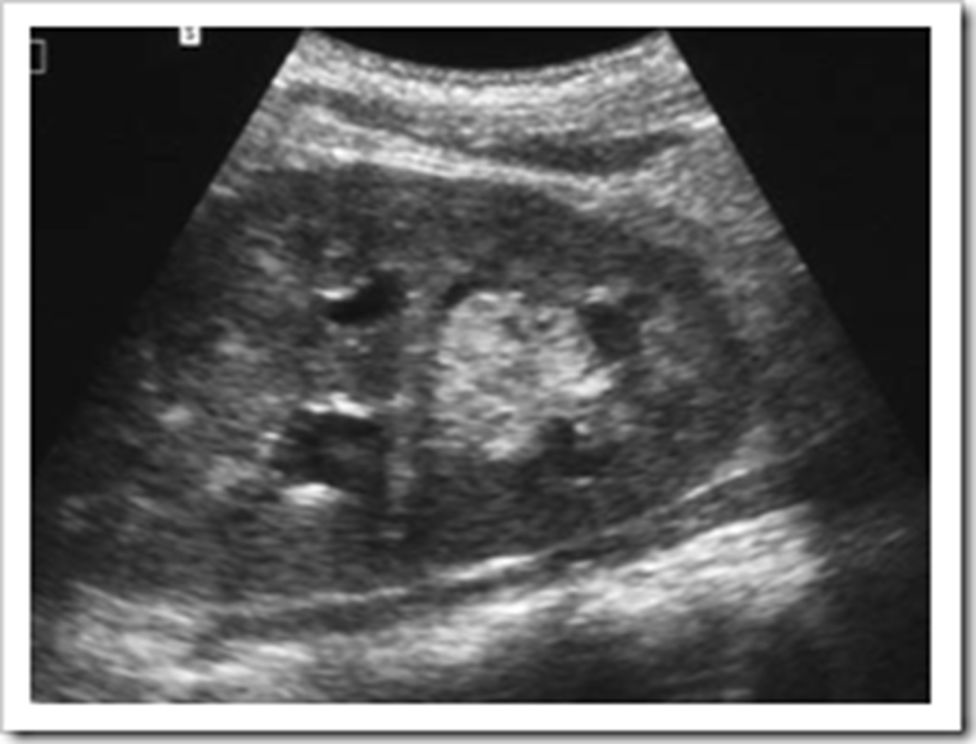

He developed an attack of anuria with rapidly rising creatinine up to 7.5 mg/dL. Urgent ultrasound revealed severe back pressure and increased echogenic contents with a distinct pelviureteric ill-defined small mass (Figure). HD started and urgent percutaneous nephrostomy was done to relieve the obstruction. Urine culture was repeated during this period and was still negative.

The child had negative urine cultures for fungal infection despite hematuria which could be explained by vascular invasion of the fungus that caused obstructed the pelvis later on by fungal mass. Renal aspergillosis is usually silent if the disease is localized to the cortex of the kidney. In this patient, fungal masse filled the pelvis of the graft causing hydronephrosis and later on obstructive anuria.

Diagnosis of this patient was provisionally made upon characteristic songraphic graft finding and was confirmed by fungal culture of the nephrostomy urine sample. Culture of the urine on Sabourad’s dextrose agar grew granular, brown–green colonies with a white apron suggestive of A. fumigatus.